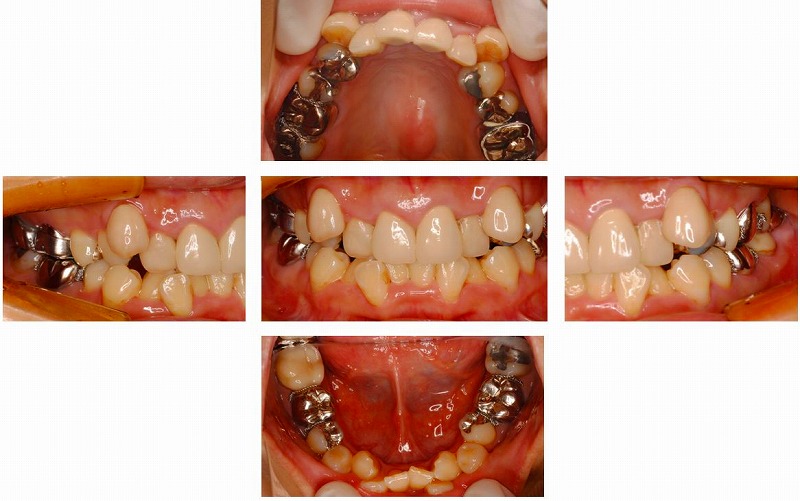

下の写真をご覧頂くと、かなり前歯が重なってる叢生(そうせい)という状態でした。

一般的には、八重歯とか言います。このようにかなり叢生が強い時には、やむなく

抜歯をして隙間を作り、その分を重なりの解消に使います。

最終的な治療結果は隙間のない綺麗な一列の歯並びになるというとこになります。それが昨日の写真(この下の写真)です。

見比べて頂くと、劇的に変化しているのがお分かり頂けると思います。